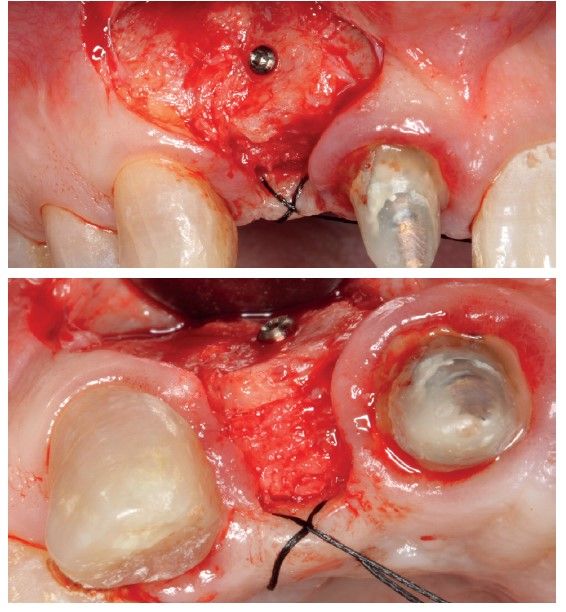

To continue with the study of the case, a Cone Beam is performed where we can observe three-dimensionally the position of the implant located in position 1.2. In the sectional cuts it is visualized completely positioned toward vestibular with an almost complete resorption of the cortical bone of this area, which explains the underlying soft tissue problems. The periapical radiography shows the position of the implant with respect to adjacent teeth (Figures 5 and 6). With this image we proceed to create a flap and the explantation of the implant. The crown located in tooth 1.1 is also removed to be able to make another crown that will serve to support the provisional extension for zone 1.2, while the first procedure heals. In this first approach a block grafting obtained from the mandibular ramus is also placed which is fixed with a microscrew in the area to be regenerated where the vestibular cortical has been lost. Once fixed and positioned, it is filled around the block grafting with particulate bone obtained with a bone-scraper of the same donor zone embedded in PRGF-Endoret for better fixation and cellular viability (Figures 7-9).